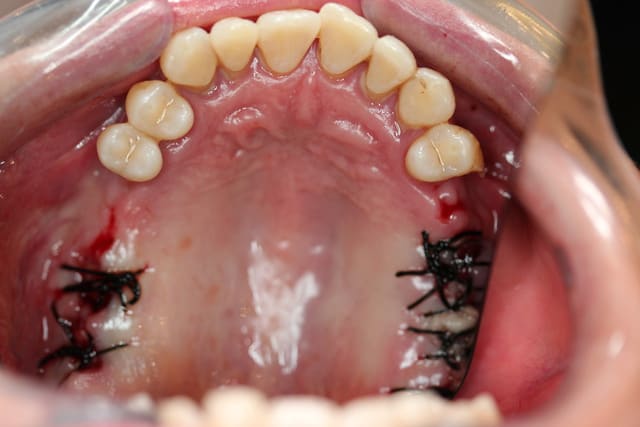

Voici

A toi de juger si la paro peut encore qqch pour cette patiente

A titre purement informatif : mobilité de type II et III de partout ;-)

Il et clair Pp que le cas que tu nous montres est dramatique. D'autant plus dramatique que la solution implantaire ne sera malheureusement pas une solution de long terme.

D'un autre côté, les photos cliniques que tu nous joins montrent clairement que même si la patiente a subi un ttt paro il y a 10 ans, elle n'a en toute certitude pas continuer son traitement de maintenance !

Le traitement des parodontites et d'autant plus quand elles ont un caractère aussi aggressif implique un suivi et traitement régulier du patient. Sans cela, c'est l'échec assuré.

Amicalement

Olivier